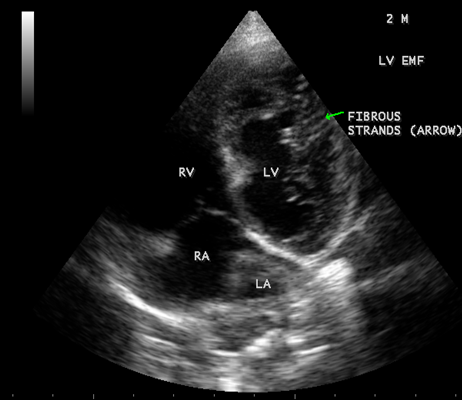

Case 6. Left ventricular endomyocardial fibrosis mimicking as Apical left ventricular hypertrophic cardiomyopathy in a 2- year old male child as shown in Figures 23 , 24 and 25.

Figure 24: Apical four chamber view showing the endocardial fibrosis of the left ventricle in a 2-year old male child

Figure 25 Apical four chamber view showing diffuse endocardial fibrosis of left ventricle in 2-year old male child.

When the endocardium is replaced by collagenous fibrosis (consist of collagen deposition and fibroblast proliferation), the final fibrotic stage is reached after several years of disease activity. Fibrotic obliteration of the apices of the affected ventricles is the hallmark of the disorder and fibrosis involving the papillary muscles and chordae tendineae leading to atrioventricular valve distortion and regurgitation. In the left ventricle, the fibrosis extends from the apex to the posterior mitral leaflet, usually sparing the anterior mitral leaflet and outflow tract and cause PML (posterior mitral leaflet) distortion and regurgitation. Like the peculiar geographical distribution, the fibrotic endomyocardial involvement stops short of the ventricular outflow tract like a ridge [17] as shown in Figures 15,29,31,35 and 44. The fibrotic tissue often creates a nidus for thrombus formation, which can be extensive. Atrial thrombi also occur and the right atrium may be aneurysmally dilated. Aneurysmal right atrium with spontaneous echo contrast was detected in a 32- year old male as shown in Figure 36 [18- Figure 3]. In addition, there are fibrosis and granular septation extending into the underlying myocardial tissue and myocyte hypertrophy is common [19]. Fibrotic process causes tethering of leaflets into ventricular walls and may mimic Ebstein’s malformation as shown in Figure 38[20],[21]. Fibrosis increases the stiffness of the heart, resulting restrictive physiology, AV (atrioventricular) valve regurgitation which has been linked to atrial arrhythmias such as atrial fibrillation as shown in Figures 19 and 20 in a 62-year old female. Atrial fibrillation has been reported in more than 30% of patients with EMF. Fibrosis impairs activation patterns of the conduction system and may provide substrate for wave breaks and reentry [22]. Fibrosis reduces conduction velocity and cause conduction abnormalities like junctional rhythms, heart blocks as shown in Figure 21 and 22 in a 75-year old female and atrioventricular conduction delay [23].

Today echocardiography is used as the screening tool at the community level as the diagnosis of EMF could be confirmed at the bedside. Echocardiography accurately assesses the pathological abnormalities of chronic disease and it is the gold standard technique for the diagnosis of EMF [36]. It reveals dense endomyocardial echocardiograms along different parts of the mural and valvular endocardium and AV valve dysfunction [37] as shown in Figures 3 to 44. The typical feature of EMF is the obliteration of trabecular portion of the ventricle and in advanced cases, there is shrinkage of the cavities creating an apical notch, regurgitation, slow flow with spontaneous echo contrast as in Figure 36 and considerable pericardial effusion. Similar to apical notch of right ventricle, a right atrial notch is well seen as contraction (or retraction) of tricuspid annulus as in Figure 40 and right atrial notch as in Figure 41 and 42, indicating the retraction of rightatrial cavity as a peculiar feature of right ventricular EMF. Biventricular enlargement as shown in Figure 40 and biatrial enlargement as in Figure 32 are the characteristic features of advanced stage of EMF. The fibrosed muscular trabeculae extending into the cavities from the walls of the chambers in the right ventricle visible as ‘cobra heads’ as in Figure 4 and in pericardial sac as in Figure 29, in the left ventricle. Aneurysmal right ventricle with scattered areas of fibrosis in the sub tricuspid region and a notch in the right atrium is well seen in a 14 –year old boy as in Figure 42 . Right atrial notch is frequently noticed in EMF patients as shown in Figure 41 in a 47- year old male with left ventricular EMF and moderate pericardial effusion.